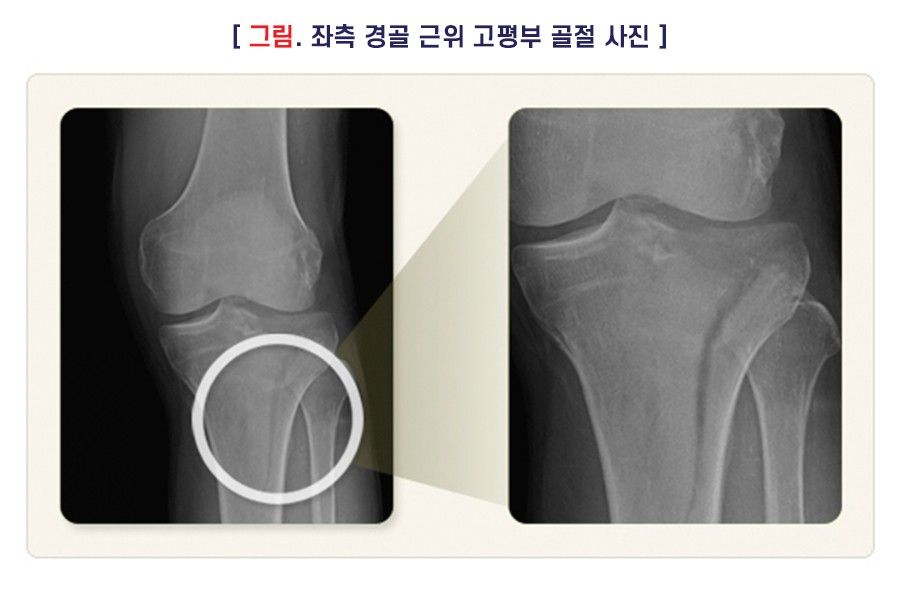

근위(부) 경골부 골절은 축방향이나 측방향에 무게가 실리거나 두 현상이 함께 일어나면서 대퇴골이 경골(정강뼈)에 부딪쳐서 경골 고평부(근위(부) 관절면) 골절이 발생하는 경우가 많습니다. 외측 경골의 골절이 내측에 비해서 많이 발생하고, 노인의 뼈와 같이 약한 뼈에서는 함몰 골절이 일어나기 쉽습니다. 골절 외에 인대나 연골판, 신경, 혈관과 같은 연부조직 손상이 동반될 수 있으므로 주의하여야 합니다.

전위가 없거나 아주 적을 때는 보조기 등을 이용하여 비수술적 치료를 시행하기도 합니다. 하지만 전위된 관절 내 골절은 대부분 수술적 치료가 필요하며, 나사못과 금속판을 이용한 내고정 및 외고정을 단독 또는 함께 시행할 수 있고, 필요 시 관절경의 도움을 받을 수 있습니다.